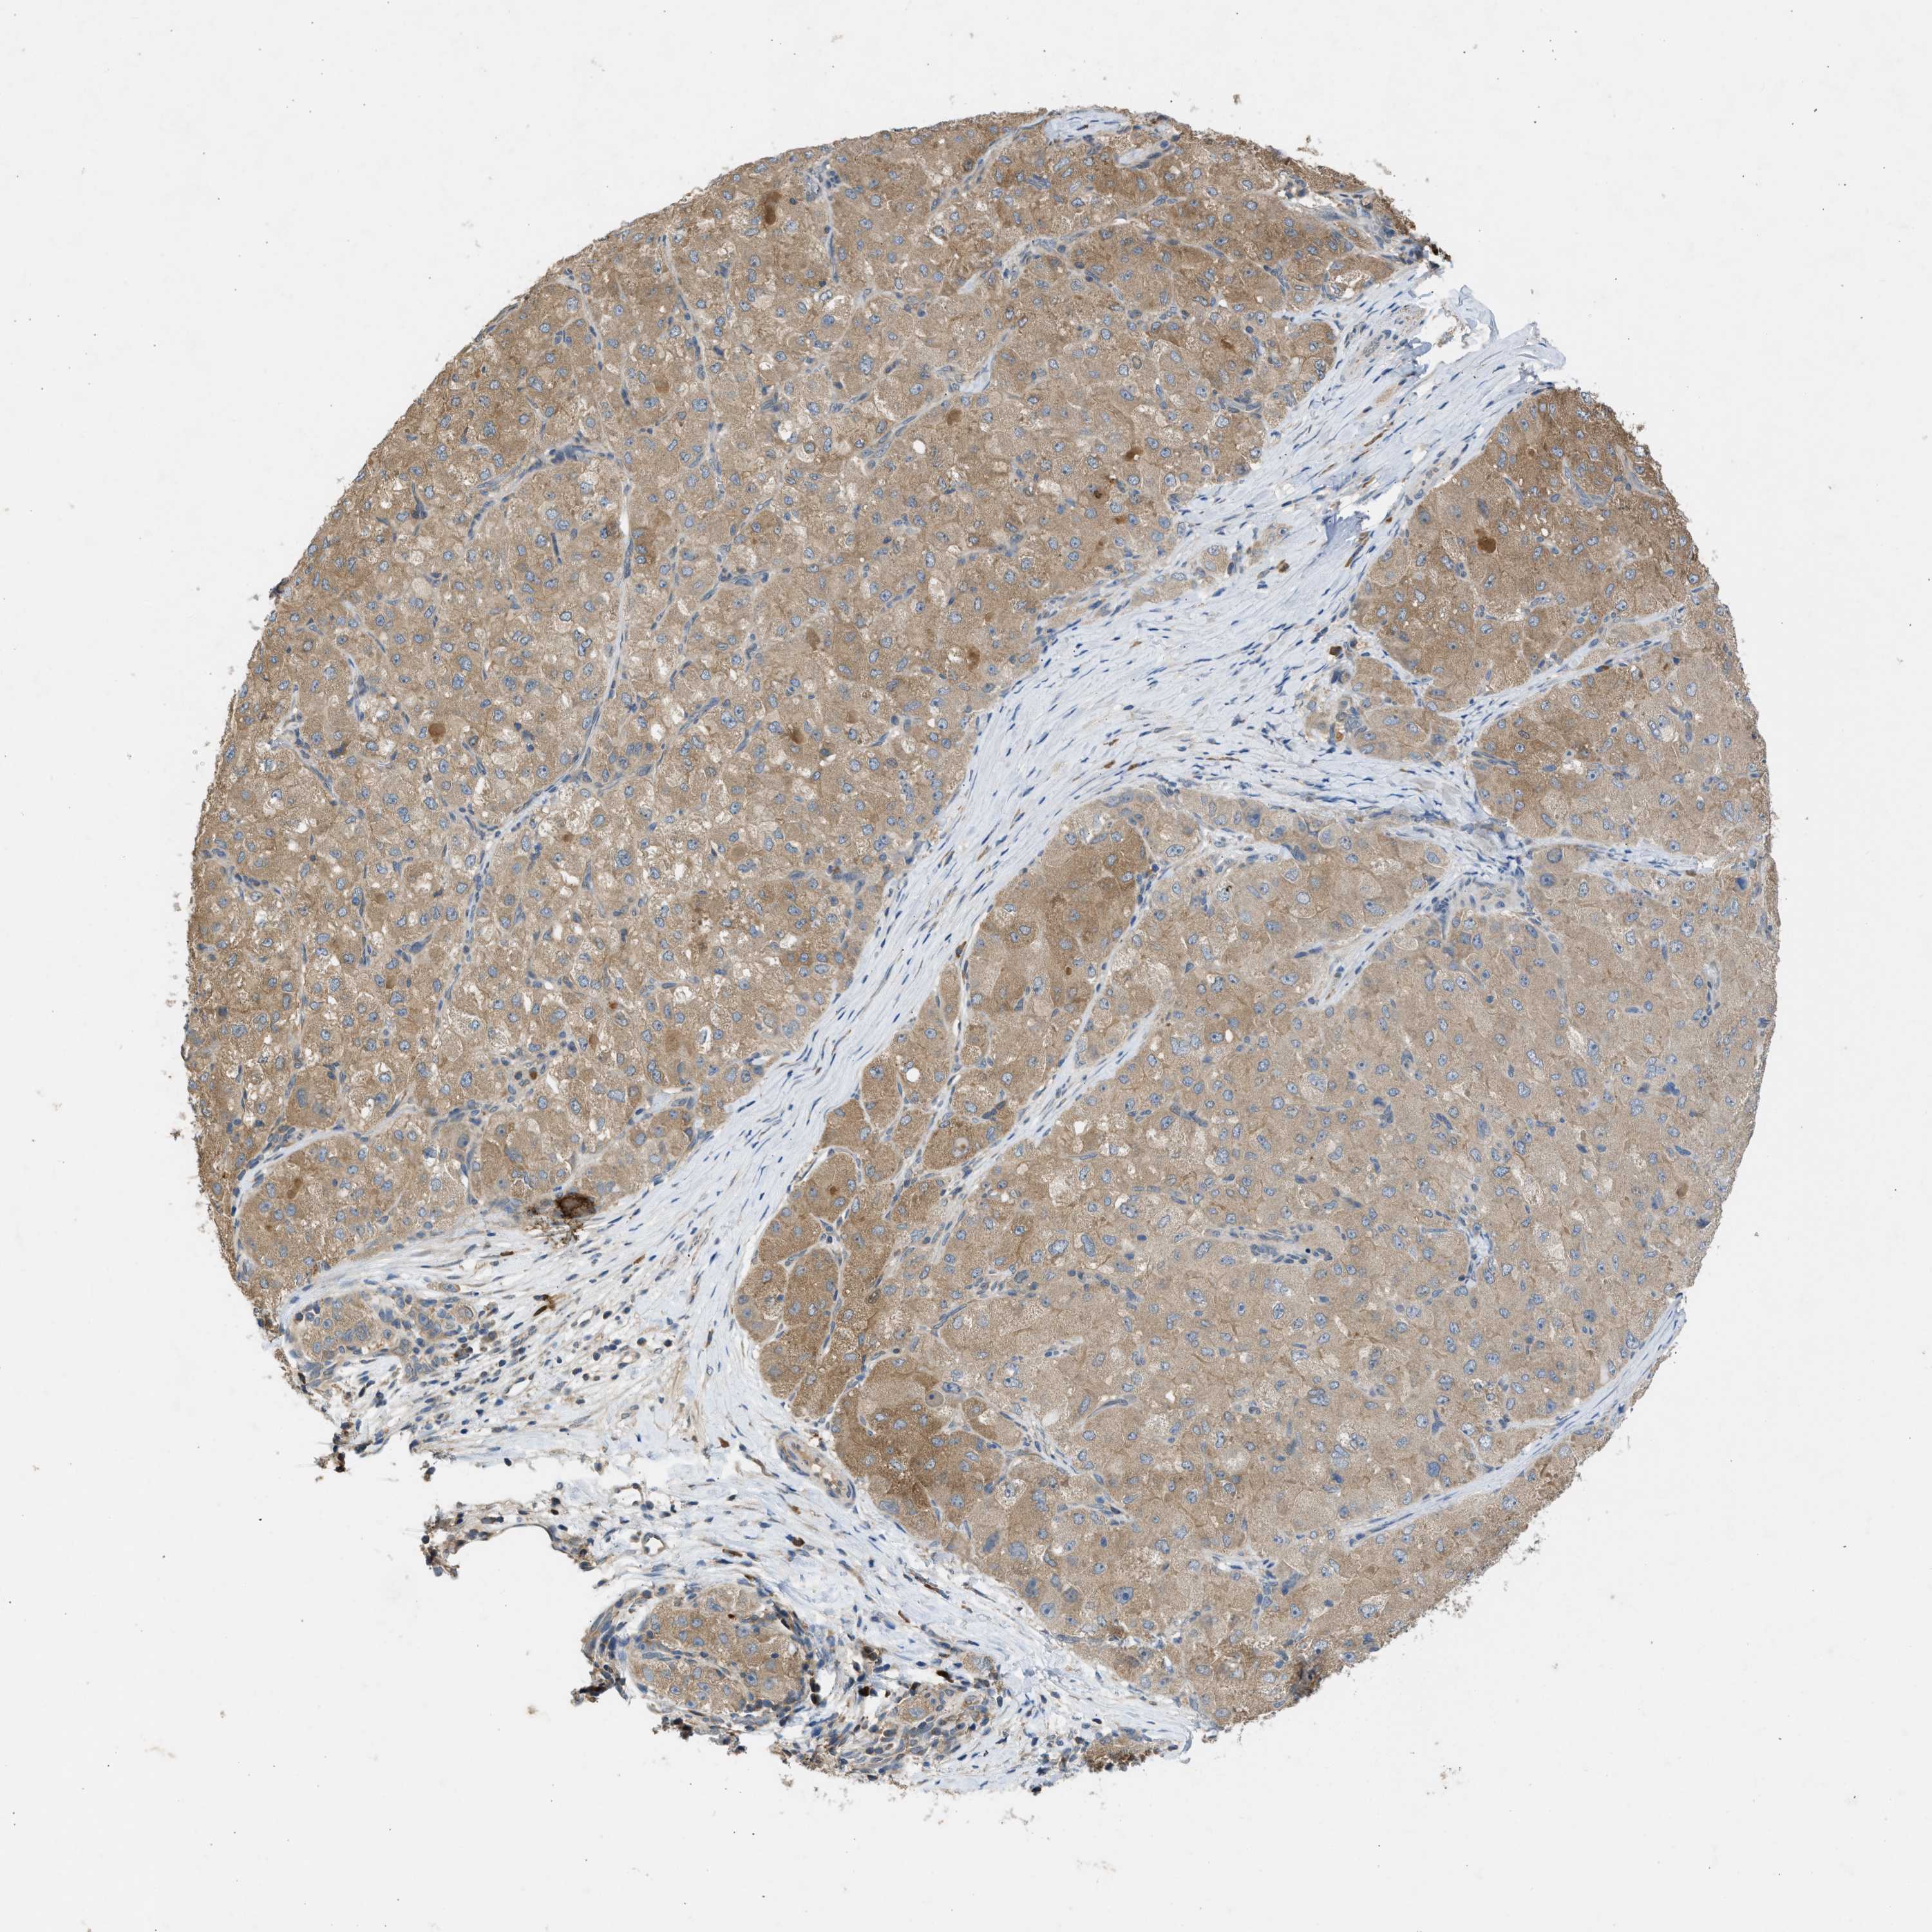

LIVER CANCER - Protein expressioni

A mouse-over function shows sample information and annotation data. Click on an image to view it in a full screen mode. Samples can be filtered based on level of antibody staining by selecting one or several of the following categories: high, medium, low and not detected. The assay and annotation is described here.

Note that samples used for immunohistochemistry by the Human Protein Atlas do not correspond to samples in the TCGA dataset.

Antibody stainingi

Antibody staining in the annotated cell types in the current human tissue is reported as not detected, low, medium, or high, based on conventional immunohistochemistry profiling in selected tissues. This score is based on the combination of the staining intensity and fraction of stained cells.

Each image is clickable and will lead to virtual microscopy that enables deeper exploration of all samples and also displays staining intensity scores, fraction scores and subcellular localization as well as patient and tissue information for each sample.

Antibody CAB018561

Staining

High

Medium

Low

Not detected

Intensity

Strong

Moderate

Weak

Negative

Quantity

>75%

75%-25%

<25%

None

Location

Nuclear

Cytoplasmic/membranous

Cytoplasmic/membranous,nuclear

Cholangiocarcinoma

Carcinoma, Hepatocellular, NOS